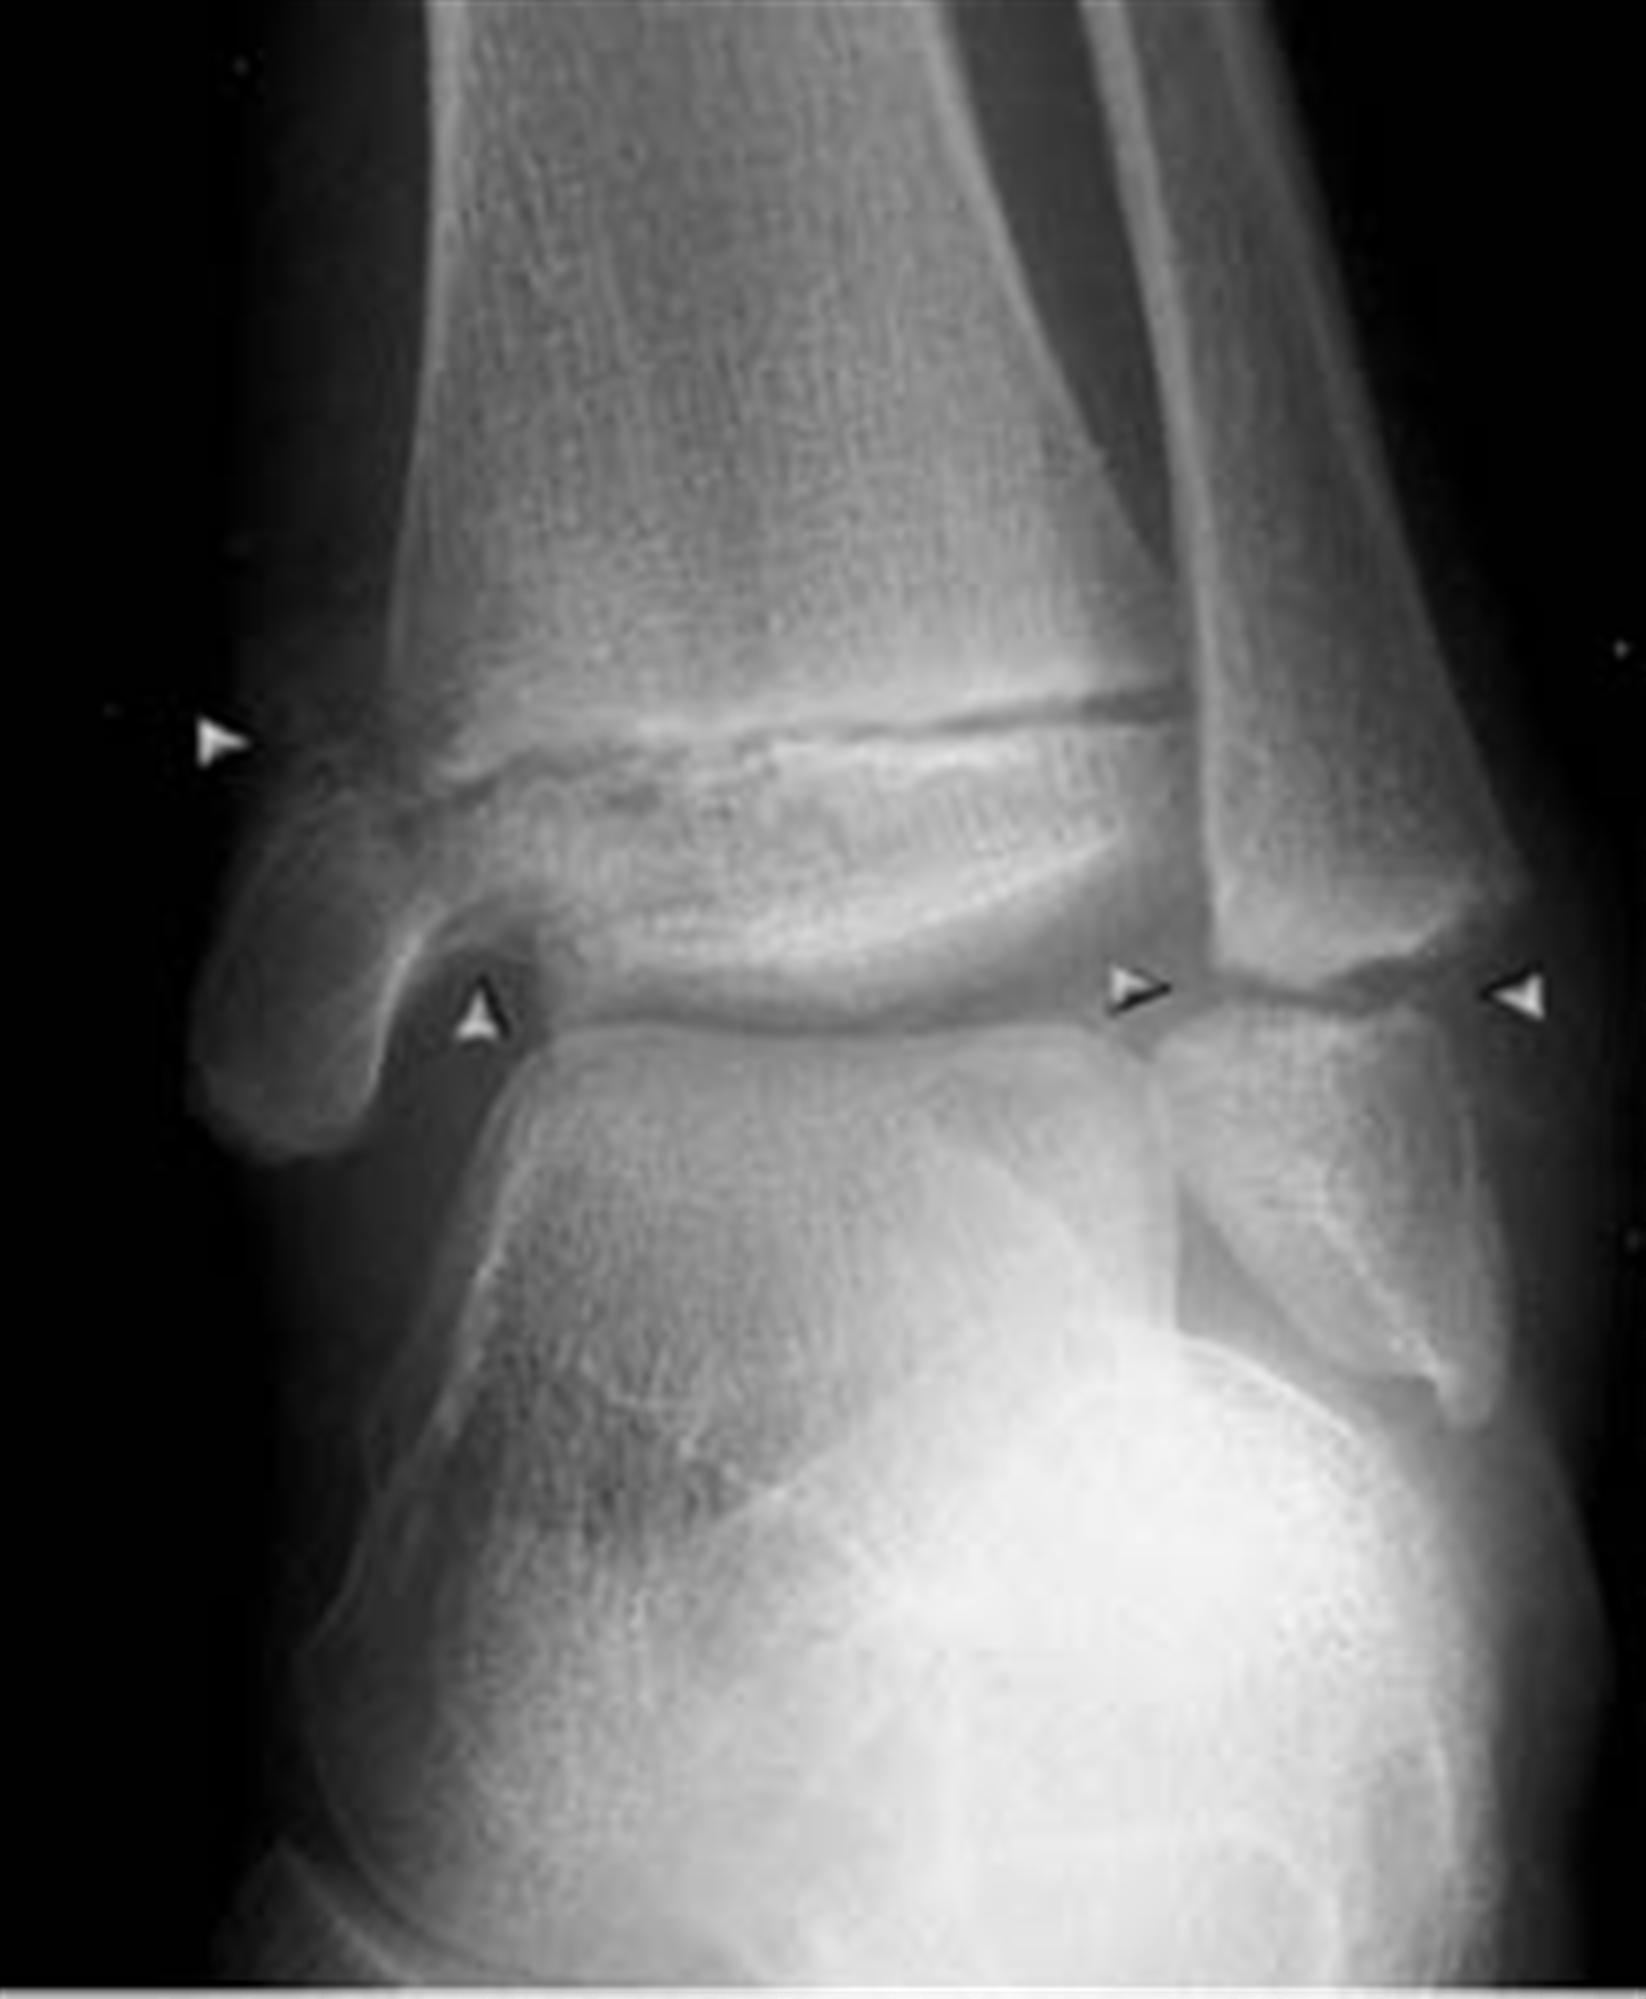

Ankle fusion is a surgical procedure that removes the surfaces of the ankle joint so that the tibia and talus bones can fuse together. Web revision ankle fusion “i, graham appleby, was in a considerable amount of pain in my left ankle when a friend recommend i go and speak to mr m herron. This can stretch or tear the tough bands of tissue.

Web the bone under the ankle (the talus) has collapsed. Web ankle fusion surgery, also called ankle arthrodesis, is when two or more ankle bones are permanently fused together. Fusion in the equinus will accentuate the postoperative limp.